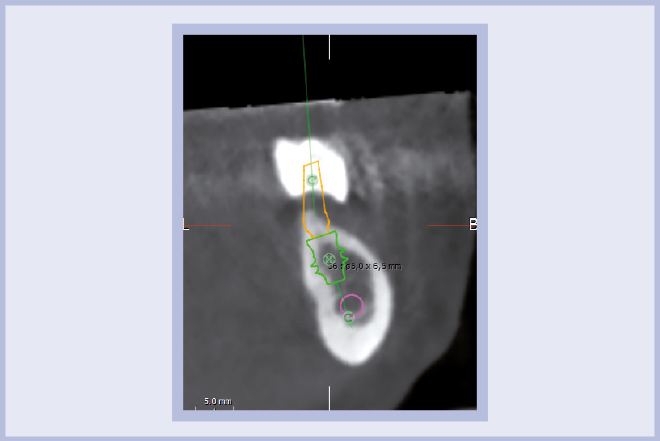

- Fig. 30 – Confronto tra posizione progettata e posizione clinica degli impianti: si noti la stretta corrispondenza tra il progetto e la CBCT post-operatoria